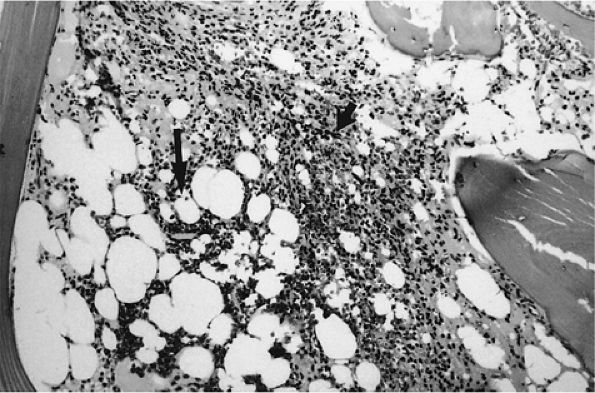

![]() |

FIGURE 13.21 ● Bone marrow cellularity is low (i.e., 40:60 cell-to-fat ratio) in hairy cell leukemia. Mononuclear cells (short arrow) enveloped in reticulin form solid areas and infiltrate between the remaining fat cells (large arrow) (H & E; original magnification × 100).